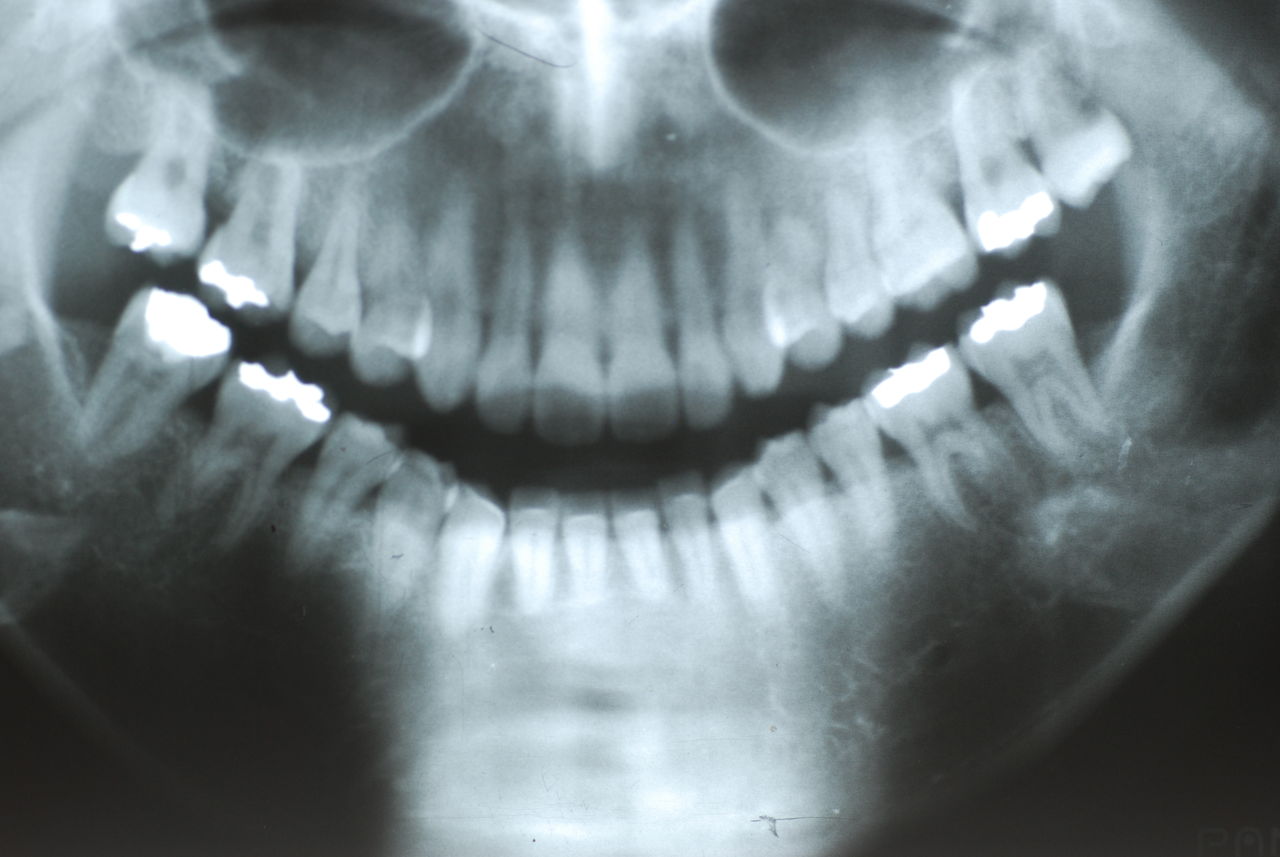

なかなかブラシの使い方ができていないようで、歯磨きと歯周病でのブラシの使い方は別なのですが、習ったことも検査もされずに金属を被せたりしているようで、これからも歯医者さんで抜かれたり、その後にインプラントのような高価な“クギ”を打ち込まれる方が増えるかと思うと残念です。

被せても、詰めても病気は治らないのですから。又病気の元になり易い不適合な差し歯や金属、インプラントがあればそこからバイキンが侵入して体に悪さもしやすいのではないかと心配しています。

歯周病と根尖病巣(根管内とは違う)の菌は同じだとか、所謂biofilm感染症なのだと。